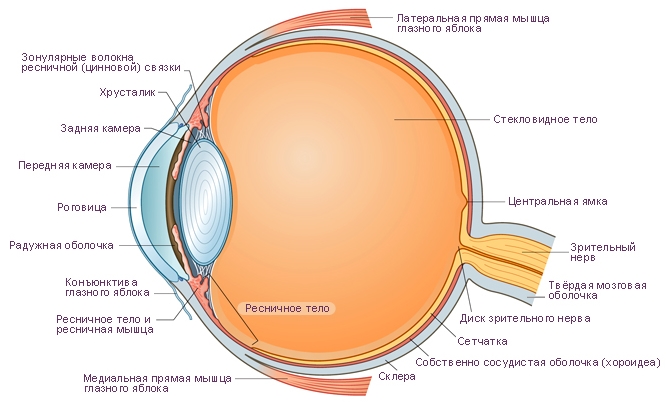

КТ-графики и изображение строения глаза